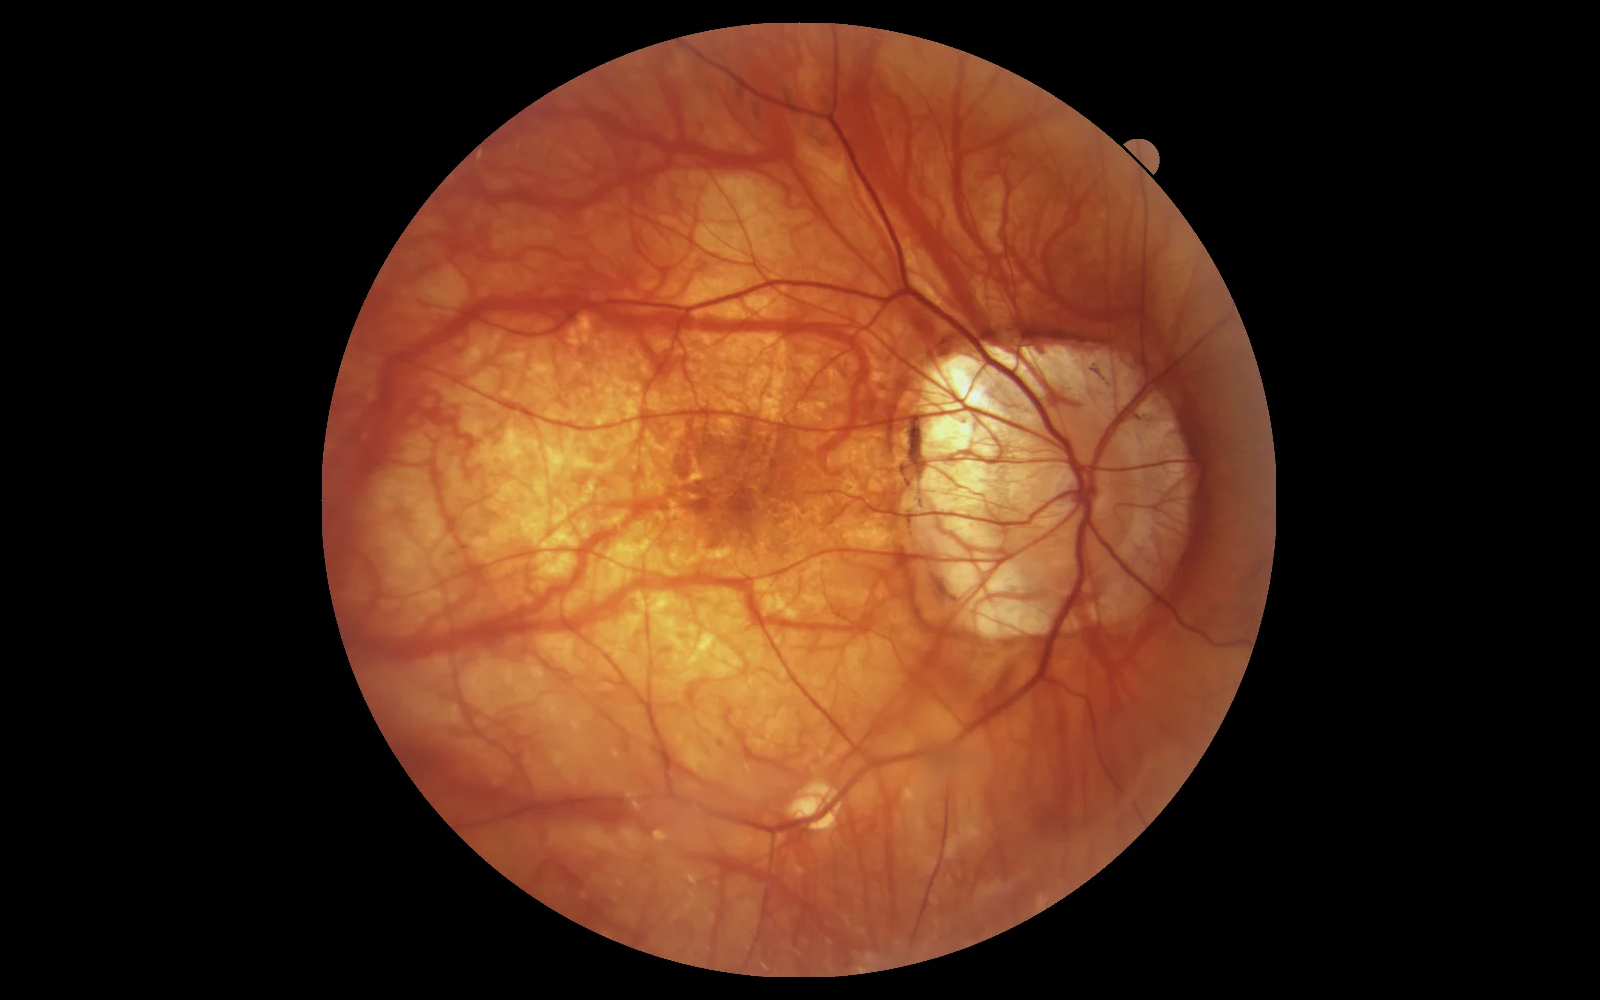

Non-Myd Color Fundus Camera

Integrated fundus and anterior imaging within a single OCT workflow

The REVO FC OCT series integrates a high-resolution 12.3 MP non-mydriatic fundus camera, enabling the capture of true-color retinal images with a 45° field of view (67.5° internal angle), delivering excellent detail and consistency. Fully automated operation — including auto-alignment, auto-focus, auto-flash, and auto-capture — ensures fast and user-independent image acquisition, even with pupil sizes as small as 3.3 mm.

The system also supports anterior segment photography, allowing documentation of corneal and anterior eye structures within the same workflow.

Fundus Analysis Tools

A comprehensive set of photo filters supports enhanced visualization and documentation of retinal conditions.

Panoramic Wide-Field Photography

REVO OCT devices with integrated fundus camera enable wide-field retinal imaging with coverage of up to 100° (~150° at the spherical center of the eye). In Mosaic photo mode, up to 9 internal fixation positions allow capture of peripheral areas and create a wide-field mosaic image — without mandatory patient dilation.

The REVO FC now enables coverage of up to 100° (~150° at the spherical center of the eye), providing a new wide perspective in retinography. In Mosaic photo mode, up to 9 internal fixation positions are available to capture peripheral areas and create a wide-field mosaic image. Patient dilation is not mandatory.